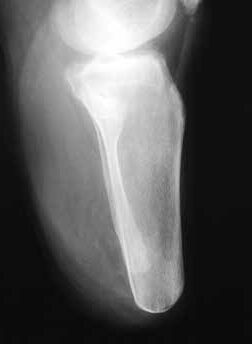

Sehr lange Unterschenkelstümpfe (kurz oberhalb der Spongiosa der distalen Tibia) sind auf die Dauer wegen der Gefahr zunehmender trophischer Störungen über die Jahre auch bei sehr geringem Endkontakt in der Prothese problematisch (Abb. 11). Viele Jahre scheint ein langer US-Stumpf gut versorgbar zu sein, wenn die Amputation im Kindesalter stattfindet und wenn Tibia- und Fibulaende sich fast auf gleicher Höhe befinden und somit eine breitere Auflagefläche für den Endkontakt darstellen (Abb. 12). Gewebe und arterielle Durchblutung stellen sich offenbar im Kindesalter auch besser auf die Gesamtsituation ein. Allgemein gilt aber: Der beste Unterschenkelstumpf ist der, der mit Muskulatur unter physiologischer Vorspannung gedeckt ist.

Die Länge des Knochens ist für die Biomechanik des Stumpfes wesentlich verantwortlich. Sie richtet sich nach der Beschaffenheit der Weichteile und der Durchblutung des Unterschenkels. Vom Knochen wird prinzipiell nicht das Periost entfernt. Die Tibia wird ventral angeschrägt, so dass besonders bei kürzeren Stümpfen noch eine breite Endkontaktfläche (Spongiosa) verbleibt (Abb. 13). Im distalen Bereich (langer US-Stumpf), also im Röhrenknochenanteil, sollte man die Knochenkanten gut brechen, damit kein zusätzlicher Druck von innen gegen die dort geringen Weichteile (Haut, Sehnen) herrscht.